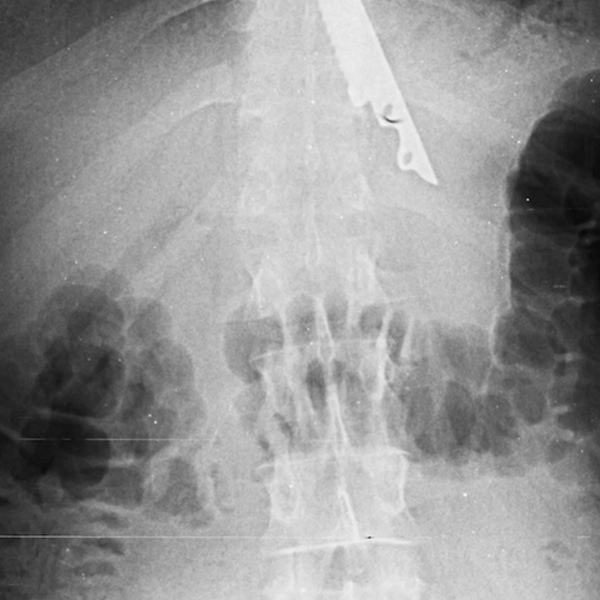

Московские хирурги спасли мужчину с 20-сантиметровым ножом в желудке

В Москве хирурги спасли мужчину с 20-сантиметровым ножом в желудке

В Москве врачи спасли пациента, у которого в желудке после пикника оказался 20-сантиметровый нож. Об этом сообщает НИИ скорой помощи им. Склифосовского.

По информации медучреждения, мужчина во время поедания шашлыка подавился кусочком мяса. Его друзья попытались помочь ему, протолкнув пищу ножом, однако острый предмет также оказался в пищеводе пострадавшего.

В результате пострадавшего доставили в медицинское учреждение, где хирурги извлекли инородный предмет из желудка пациента. Операция прошла успешно, сейчас жизни мужчины ничего не угрожает. Врачи отметили, что случаи проглатывания посторонних предметов часто происходят как по случайности, так и в результате нелепых споров.